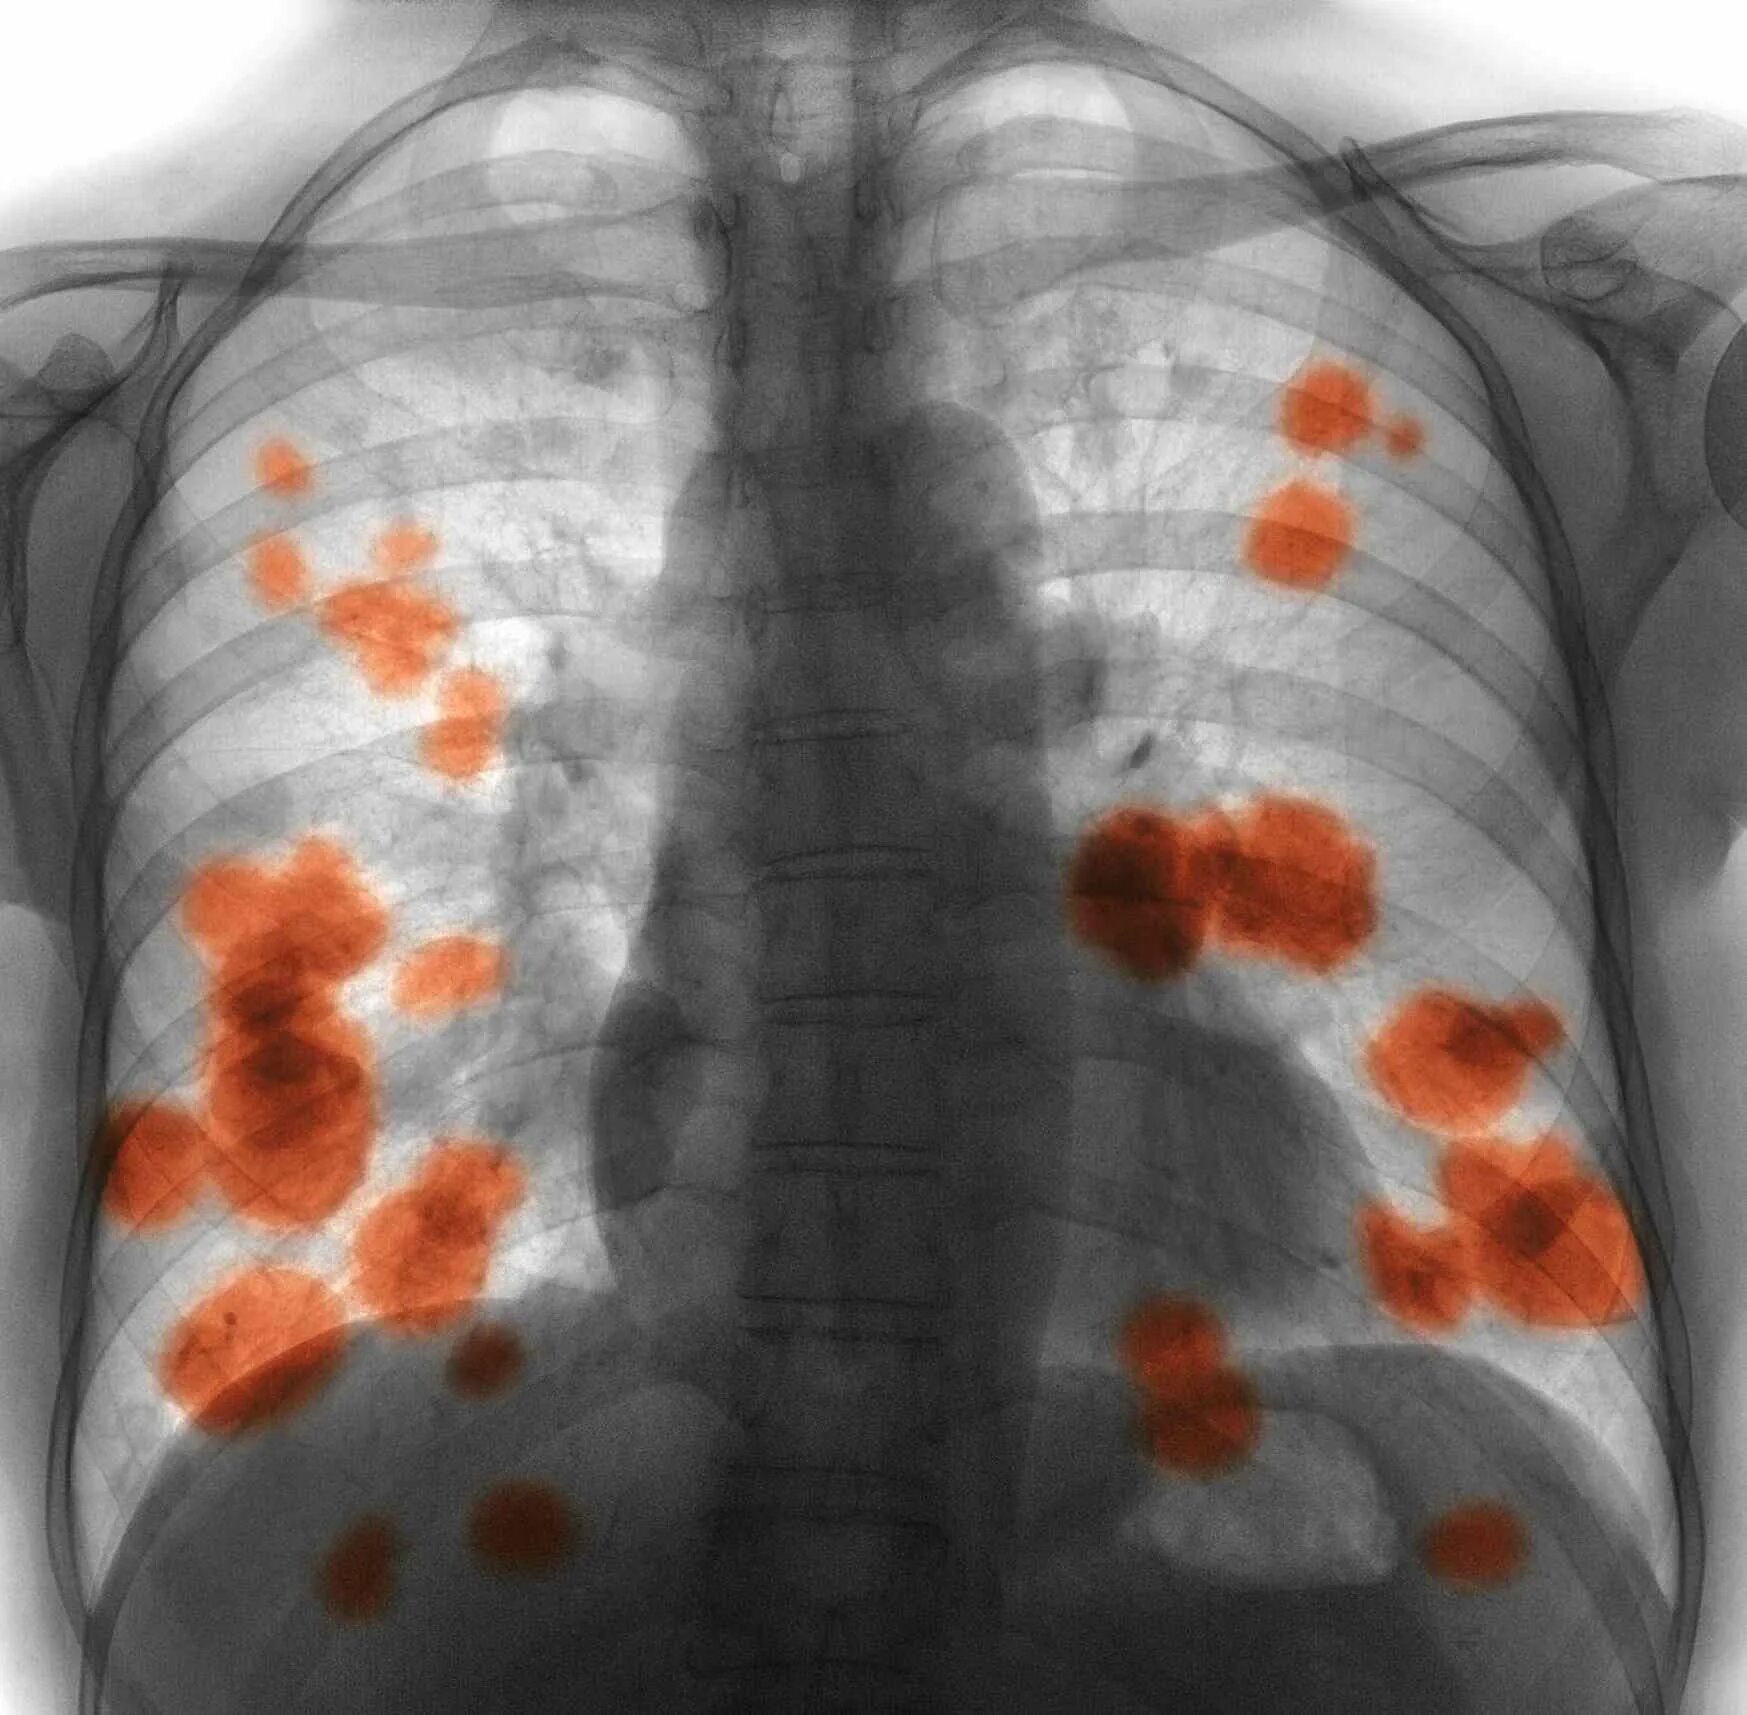

Метастазы при раке болят